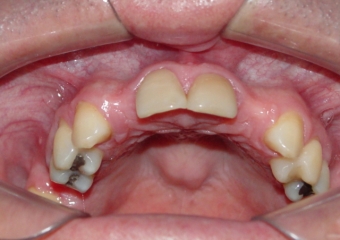

Imagens iniciais